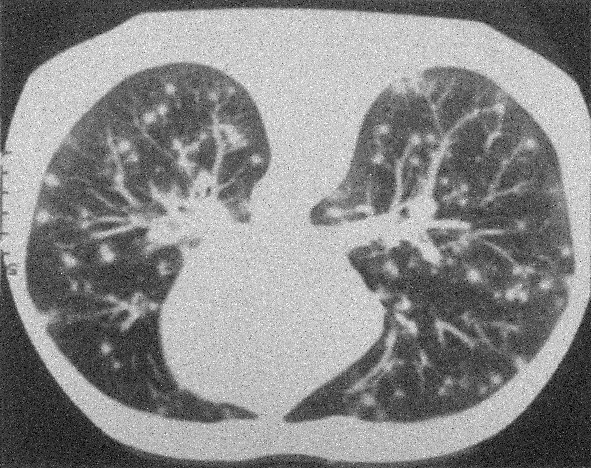

Example 2: restoration of images corrupted by blur and SPN or AWLN. In this example we evaluate the performance of the proposed TV-L1 model on three medical test images lungs (), Fig. 5 (a), ecography (), Fig. 6 (a), and aneurism (), Fig. 7 (a), synthetically corrupted by Gaussian blur of parameters band=5 and sigma=1 and by two types of impulsive noise, namely SPN and AWLN.

First, for what concerns corruptions by SPN, in Figs. 5, 6, 7 we report for the three considered test images the original and corrupted image together with the estimated -maps in the first column (with the size of the neighborhoods used for the -maps estimation reported in the captions), the restoration results, obtained by the four compared methods, in the second column (with the achieved ISNR values in the captions) and a zoomed detail of the restored images - green- bordered in Figs. 5 (a), 6 (a), 7 (a) - in the last column.

The reported ISNR values as well as the visual inspection of the restored images and of the zoomed details strongly indicate how the proposed space-variant regularizer allows for higher quality restorations. In particular, it is worth remarking how, with respect to the space-variant TV model, the additional degrees of freedom represented by the scale parameters used in our proposal, yield a sufficient additional flexibility for avoiding unwanted spurious effects - see, e.g., spikes in Figs. 5 (i), 6 (i), 7 (i).

| (a) original | (b) TV-L1 (ISNR = 22.13) | (c) zoom of (b) |

![]() |

| (d) corrupted | (e) TVp-L1 (ISNR = 23.15) | (f) zoom of (e) |

| (g) -map () | (h) TV-L1 (ISNR = 25.46) | (i) zoom of (h) |

| (l) -map () | (m) TV-L1 (ISNR = 28.01) | (n) zoom of (m) |